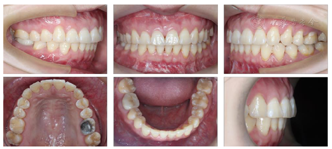

口内检查(图2):

恒牙列,磨牙关系左侧近中,右侧中性,前牙Ⅲ度深覆合,覆盖正常,下颌中线右偏1 mm,左侧前磨牙区开

。

26大面积银汞充填体,46牙色充填体。

32-43对应前庭沟处黏膜可见瘢痕。